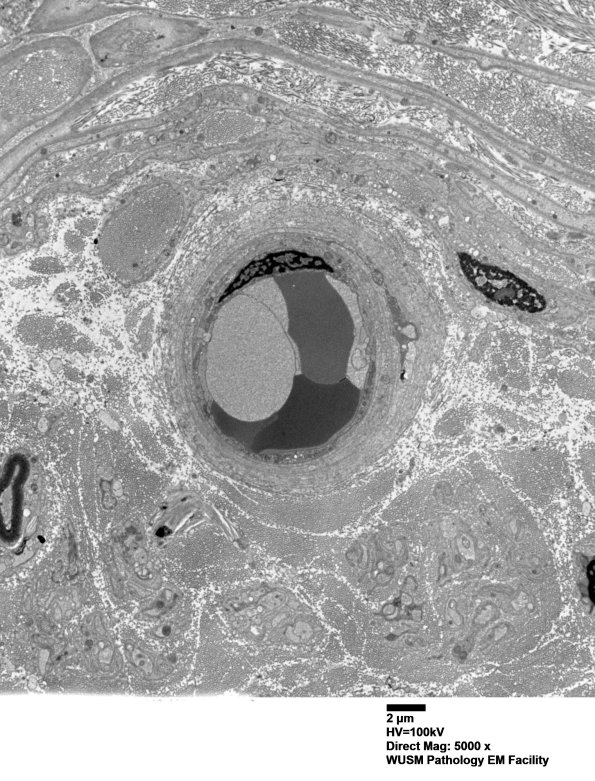

14B2A-E Multiple magnifications of a mildly enlarged vessel which has been expanded by collagen deposition. (electron micrographs)